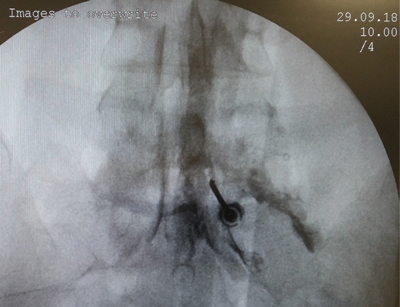

Los procedimientos fueron realizados en sala de operaciones, con anestesia local con lidocaína al 0,5 %, mediante abordaje interlaminar parasagital homolateral al dolor en los espacios L4-L5 o L5-S1, con aguja de Tuohy número 17 o 18, 3½ o 4¾ pulgadas según la complexión física del paciente, con identificación del espacio epidural mediante pérdida de resistencia con suero fisiológico. Se utilizó iopamiron como medio de contraste para visualizar el epidurograma (Figuras 1 y 2).

Fig. 1. Enfoque radiológico anteroposterior de la inyección de contraste en el espacio epidural, durante una inyección epidural de esteroides mediante el abordaje interlaminar parasagital derecho a nivel del espacio L5-S1.